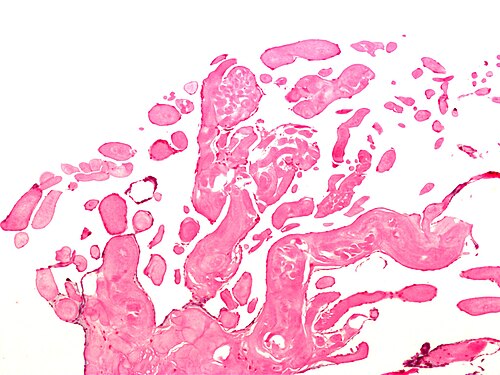

75 year old woman, dyspnea, mass on valve.

Aortic valve.

Intermediate magnification. H&E stain.

No constitutional symptoms. Mass discovered incidentally during work-up for a pacemaker.

Looks benign. Most common heart valve tumour.